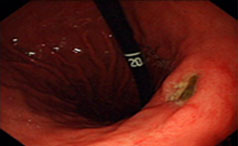

胃溃疡是指发生在胃幽门和贲门之间的慢性溃疡,是一种全球性的常见病,多发病。可发生在任何年龄段,多见于中老年人,好发于男性。胃溃疡饮食注意事项......【详情】

常见症状:体重减轻、疼痛、出血

上腹部压痛

【导语】消化系统疾病的临床表现往往不是特别典型,那么怎样才能知道是不......【详情】